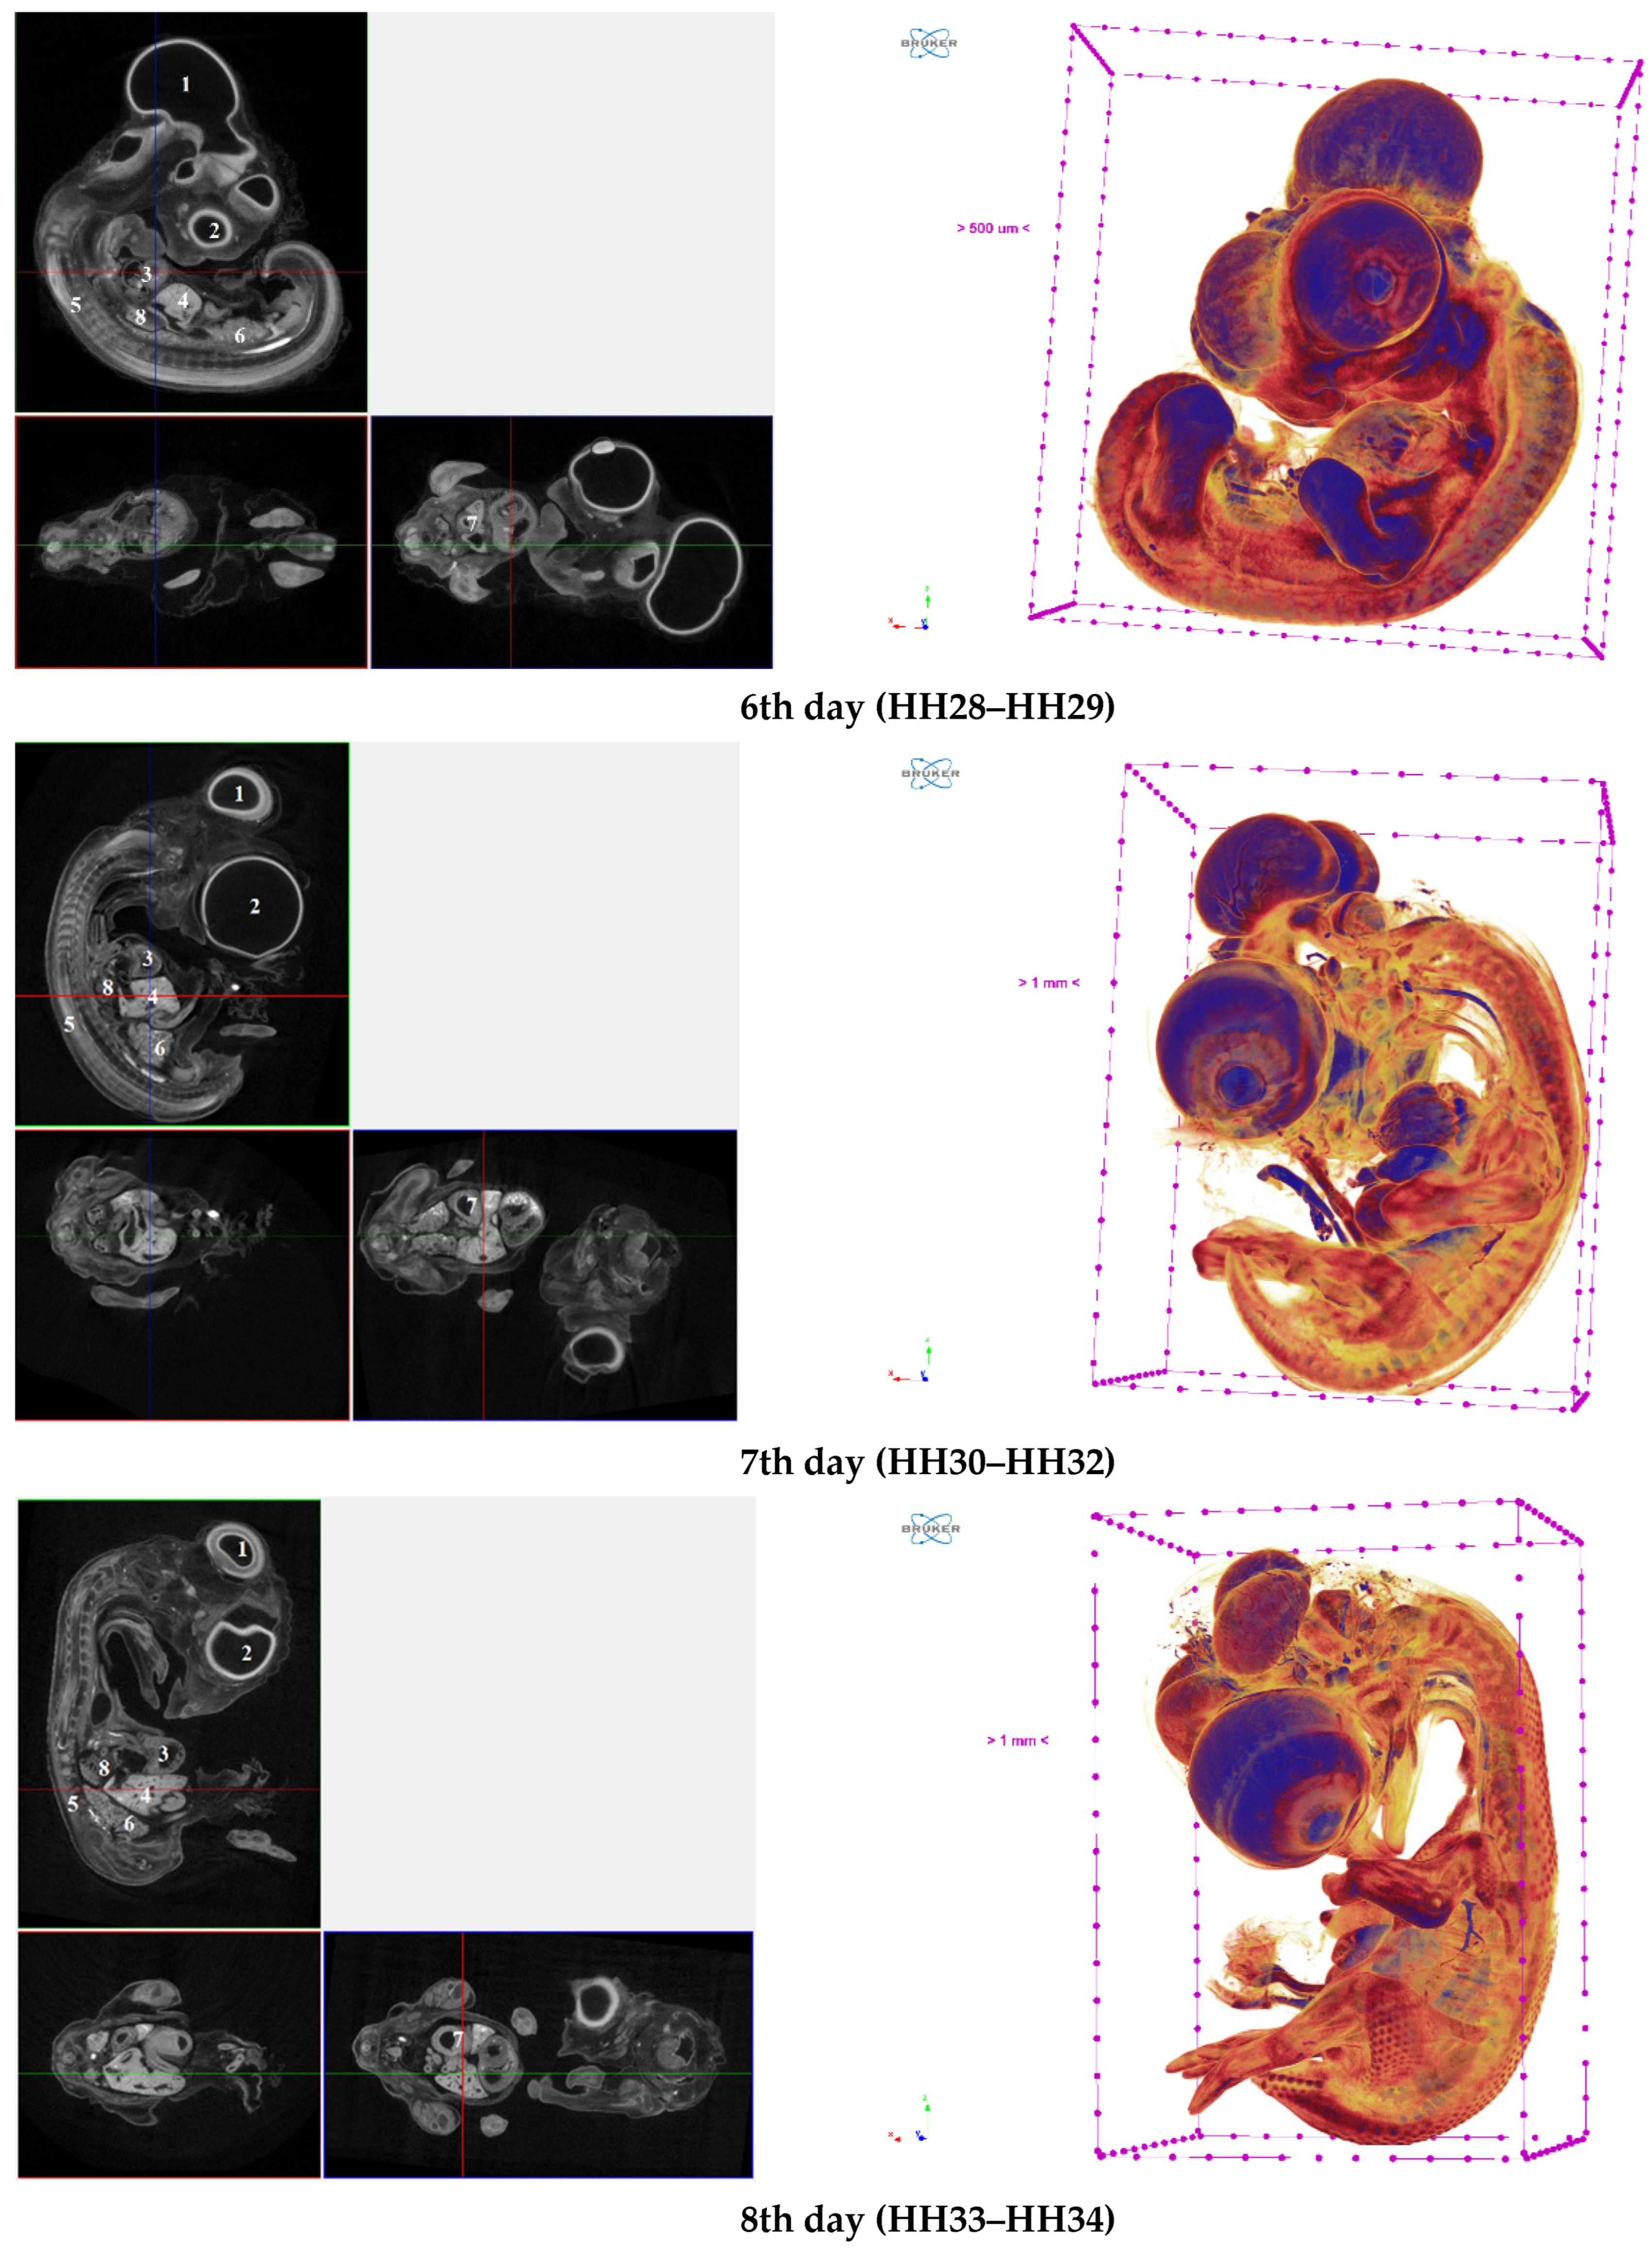

Figure 3. Representative cross-sectional images of CE (HH22–HH34 embryonic stages) counterstained with 1% PTA (left side) and isosurface 3D renderings (right side). The following organs are marked on cross-sectional images of CE: brain (1), eye (2), heart (3), liver (4), sclerotome (spine and neural canal) (5), mesonephros (6), stomach (7), lungs (8).

The findings obtained are shown in Figure 3 and Table 4, illustrating a high degree of visibility of CE organs and tissues from 4 to 8 days (HH22–HH34) when utilizing the technique of 1% PTA staining at 40 °C heating and exposure for 24 h. Filters Al 0.5 mm, Al 1 mm, and Al + Cu were utilized with a passing radiation level in most CE planes in the range of 30–50% while scanning CE at all phases of development, allowing visible separation of the surrounding backdrop from the CE structures. Simultaneously, the histogram (grey value) peaks defining the several CE organs were at a high level.

Figure 3 shows distinct contrast and numerous organs highlighted in three projections. The applied technic allowed us to obtain a high-quality 3D visualization of isosurfaces, as also can be seen from Figure 3. Furthermore, we assessed the X-ray density of several CE structures created using the recommended approach (Table 4).

Table 3 shows that during growth and development from the fourth to eighth days (HH22–HH34 embryonic stages), the total X-ray density of CE tissues prepared with the suggested method decreases. This is due to both an increase in size and a decrease in the permeability of the contrasting substance, and a change in the ratio of stroma and parenchyma in organs. From the fourth to fifth days, there was a pronounced decrease in the X-ray density of the meninges and the eye by more than two times. The total X-ray density of the embryo, as well as the structures of the sclerotome (neural canal), mesonephros and stomach also decreased by 20–30%. The X-ray density of the heart and liver structures increased to 20%. From the fifth to sixth days, the change in both the total X-ray density and individual organs and structures does not change significantly, apparently due to minor morphological changes, unlike an increase in the CE by 5–6 times, as well as with the active laying and growth of individual organs from the fourth to fifth days of incubation. From the sixth to seventh days, the general X-ray density of CE and X-ray density of almost all CE organs and tissues, except the brain, are particularly pronounced. From the seventh to eighth days, the X-ray density of the studied structures does not change significantly, except for an increase in the brain, which is associated with an increase in the volume of the meninges in its structure, the appearance of the inflection point of the lateral ventricle on the sixth day [38], as well as with a possible increase in cell density, which according to some data [35] may contribute to better stain penetration.

The visualized volume of CE generated using the recommended approach grows by 595% from day 4 to day 5, 131% from day 5 to day 6, 267% from day 6 to day 7, and 155% from day 7 to day 8 as the embryo develops. According to the findings, the brain, together with the eyes and heart, occupy over 20% of the cerebellum between the fourth and sixth days of development. The liver, excretory, digestive, and reproductive systems start actively growing on day seven. On the beginning on the sixth day of embryogenesis, the lungs may be seen. All of the data met the criteria for the growth of the embryonic phases under study.